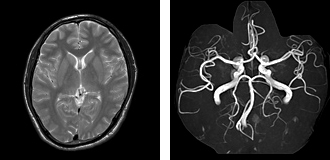

MRI検査

当院では1.5T(テスラ:磁場強度)の装置2台で検査を行っています。

MRIはX線CTよりも組織コントラストが良く、脳・脊髄や子宮・卵巣など骨盤部、乳房や関節などの検査に適しています。

X線CTのように放射線被ばくはなく、任意の断面像が得られます。

検査時間は内容により15~60分位です。検査中は大きな音がしますが、痛みを感じるようなことはありません。また、動きに弱い検査なので動かないように寝ていていただきます。